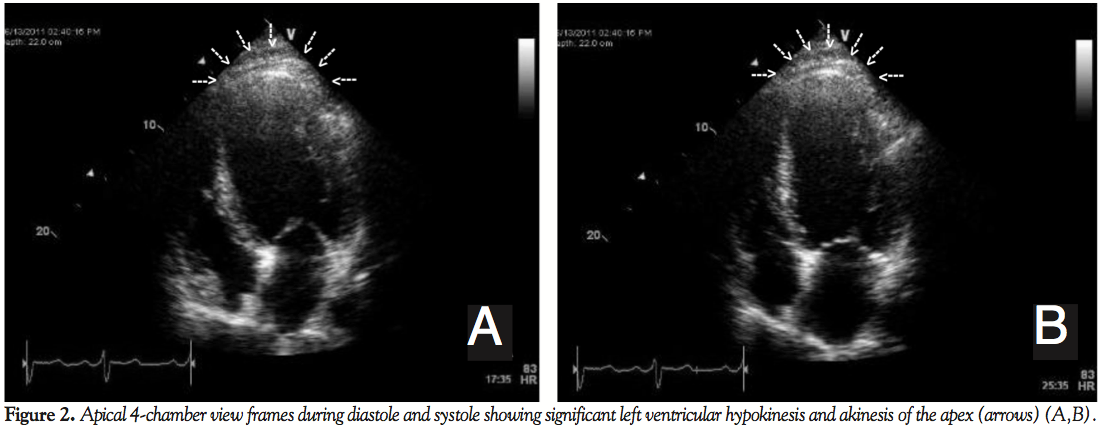

The patient’s laboratory results revealed a hemoglobin value of 13.4 gm/dL. The ECG shows normal sinus rhythm, left axis deviation, borderline left ventricular hypertrophy with nonspecific intraventricular conduction delay, and poor R progression in the precordial leads, suggestive of previous anterior wall MI (Figure 1). The echocardiogram (Figures 2A and 2B, Videos 2A-2C) demonstrated a severely depressed left ventricle ejection fraction of 25%-35% with diffuse hypokinesis of the left ventricle mild segmental wall motion abnormalities, and akinesis of the apex. There was no significant valvular pathology identified.